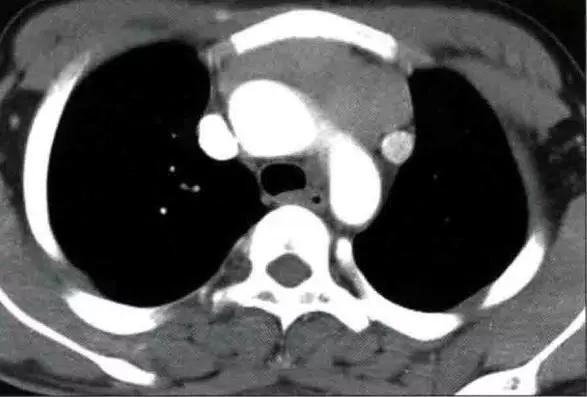

胸腺癌影像表现为前纵隔大的肿块,通常边界不清楚,边缘不规则或分叶状,常侵犯并推移邻近结构。常有坏死、出血和(或)囊性变,10% ~ 40%在CT上可见灶状钙化。常侵犯心包、胸膜并出现心包和胸腔积液

胸腺类癌影像表现与常见胸腺上皮肿瘤相仿。当前纵隔肿块伴有库欣综合征时,诊断上应首先考虑为胸腺类癌。MRI上T2WI呈明显呈高信号,可能提示神经内分泌癌的诊断